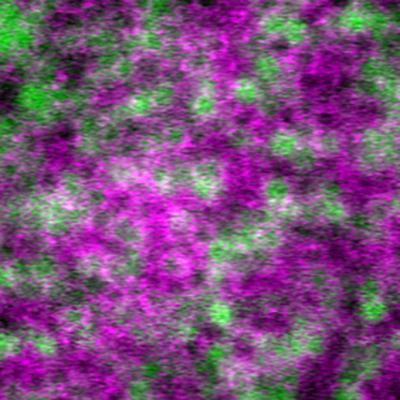

Erythrocytes in stasis captured within the choriocapillaris (green) and overlying parafoveal retinal capillaries (magenta). Read the associated publication.